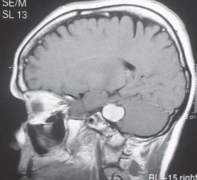

复发性较大听神经瘤手术全切案例:较大听神经瘤手术治疗具挑战性,因为此类患者通常表现为多发性颅神经缺损和脑干受压或颅内高压症状。治疗岩骨严...

听神经瘤案例|听神经瘤的临终自述,35岁的小明在察觉自己左耳听力下降后去医院做了个核磁检查,这一下,就把在他脑子里作祟的家伙给照了出来,小明...

另一方面,到达三叉神经的神经鞘瘤的特征是疼痛和面部麻木。同样,Samii和Matthies报道,大约1%-3%的前庭神经鞘瘤患者出现三叉神经痛症状。目前,医学影...